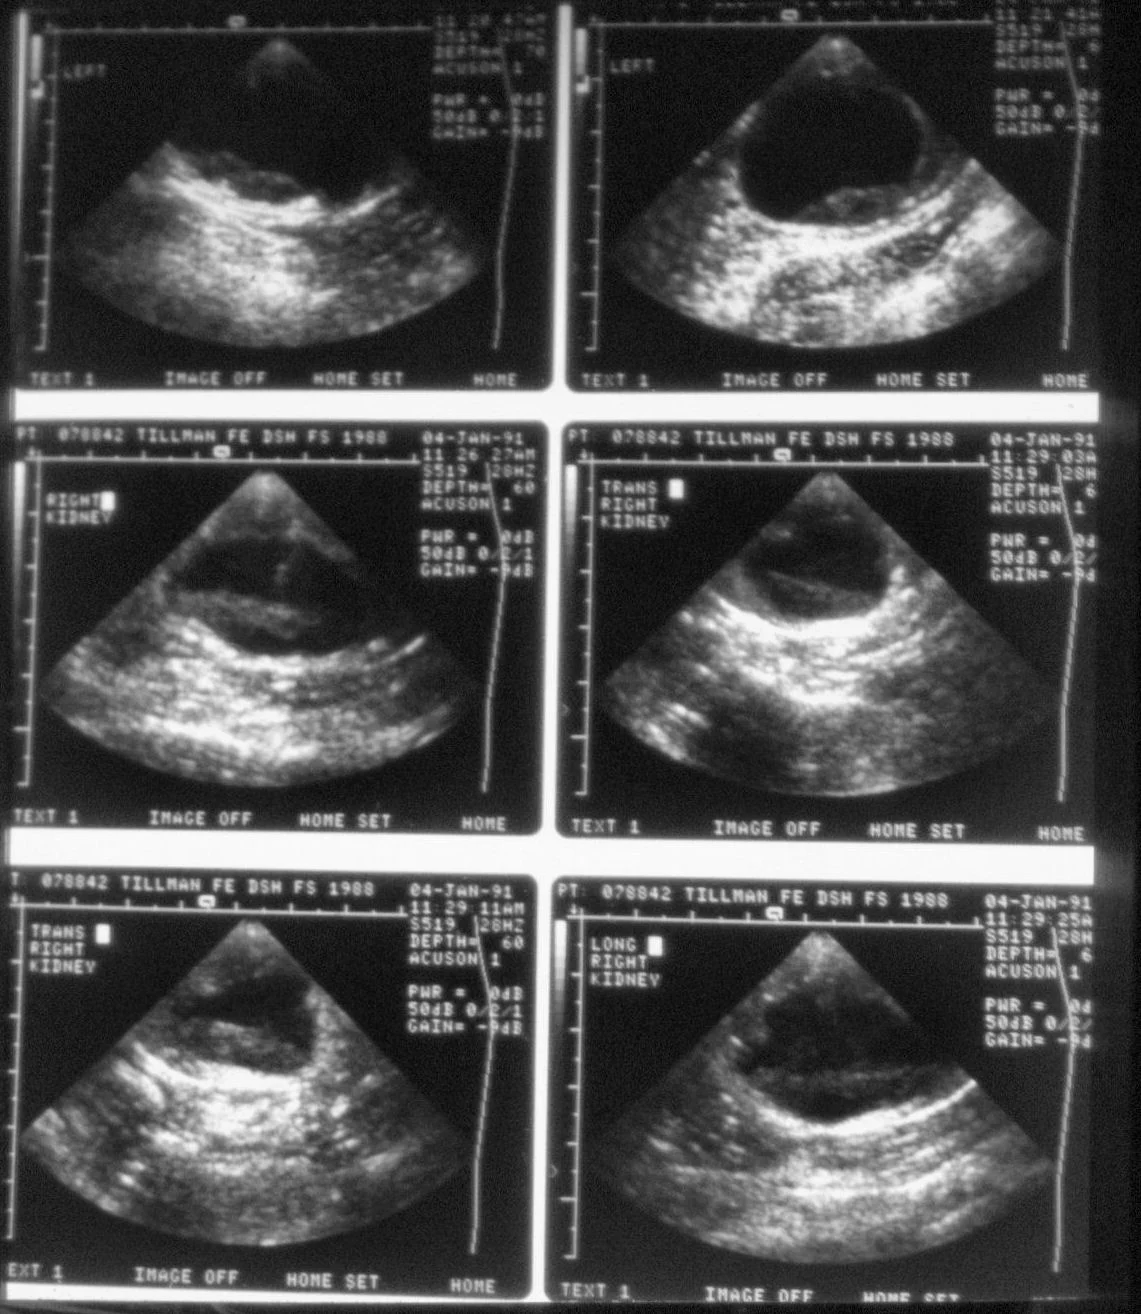

Abdominal radiographs will show only an enlarged kidney or kidneys (Figure 2A), but excretory urography will show renal pelvis dilatation (Figure 2B). Ultrasonography will also show hydronephrosis, renal parenchymal disarray, and necrotic debris in the renal collecting system (Figure 3).

Abdominal radiographs of a cat with bilateral pyonephrosis; a cystotomy performed 6 months previously had caused bilateral ureteral obstruction at the urethral junction (A and B). Pyelography was done by pyelocentesis, and bilateral hydronephrosis is shown.

Abdominal ultrasonography (from patient in Figure 2) showing hydronephrosis and necrotic debris in both renal pelvises (A); close-up view of the right kidney (B).